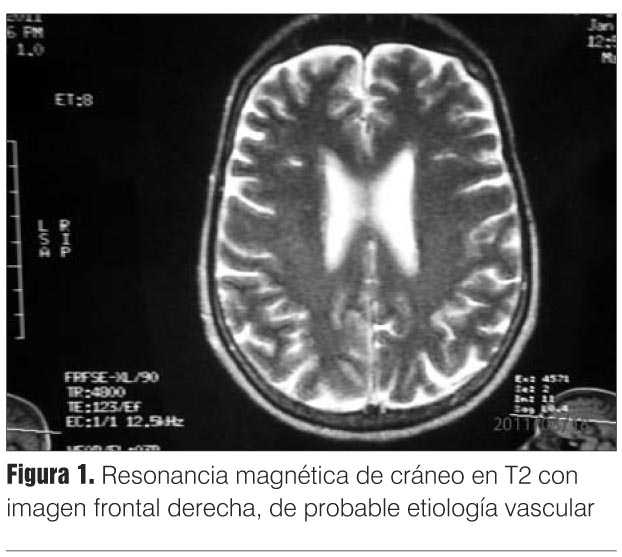

Con el planteo de proceso expansivo infratentorial lateralizado a izquierda, se solicitó resonancia magnética (RM) de cráneo que descartó esta hipótesis diagnóstica mostrando un aumento de la señal en Flair y T2 en región frontal derecha de probable etiología vascular (figura 1).